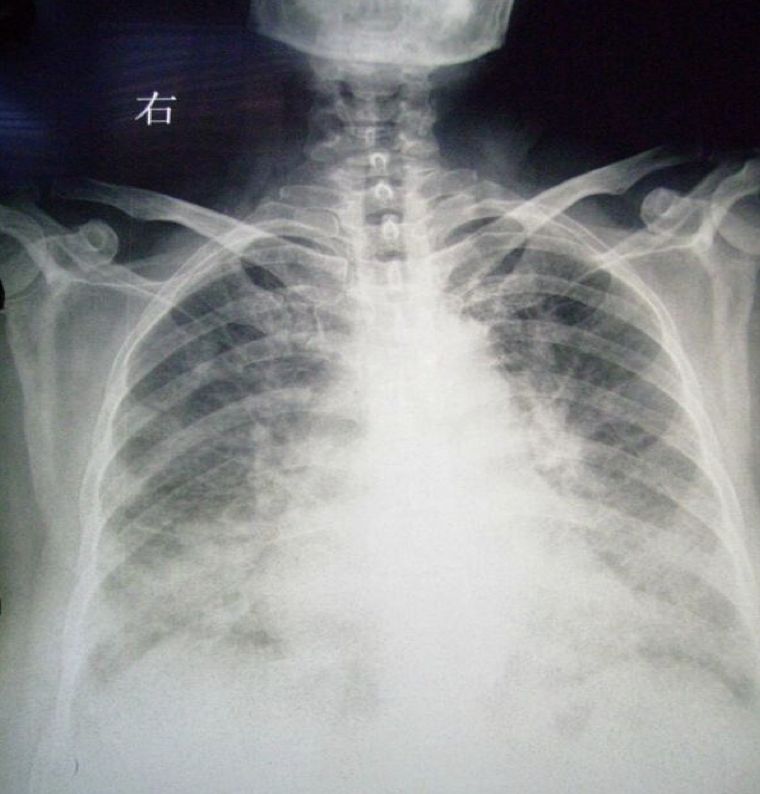

➤ 急性肺水肿